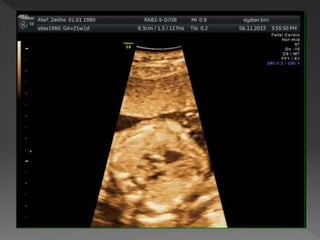

 Diyaframın hemen üzerinde toraksın

tranvers kesiti ile elde edilir

 Fetusun oryantasyonuna bağlı

apikal, lateral ya da ters apikal

görüntü alabilir

 Tümü analiz yapmak için uygundur

 Fetal omurga aşağıda olduğunda

ideal olarak görüntülenir